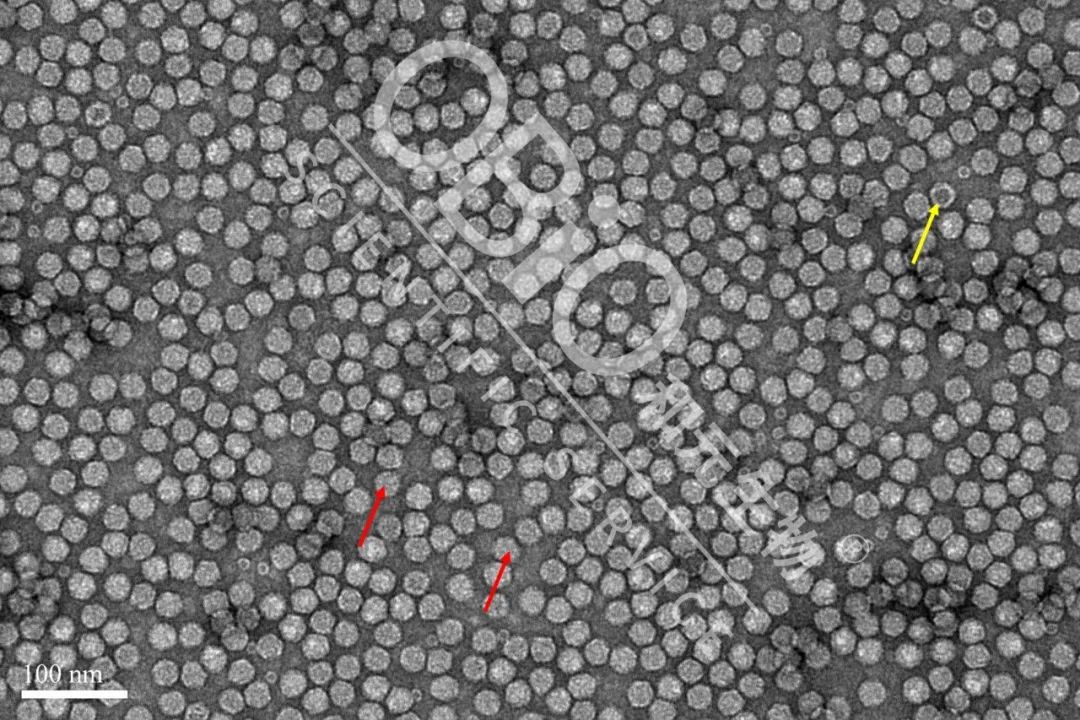

图2 rAAV载体生产空壳率大比拼

为了更好地显示中国-九游·会J9官方网站|真人游戏第一品牌 AAV产品的属性,我们选取大视野进行比较

图3 中国-九游·会J9官方网站|真人游戏第一品牌 rAAV载体生产空壳率

电镜结果:包装DNA基因组的病毒颗粒为实心颗粒(红色箭头);空病毒颗粒中间存在空洞(黄色箭头)